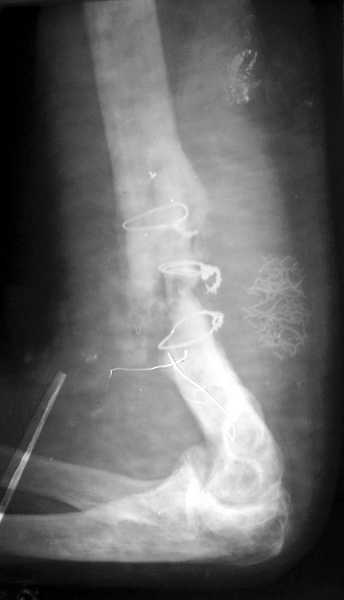

На примере два случая, извиняюсь за качество снимков, снимки и случаи из бывшего союза.

Первая больная с "успехом" была прооперирована 6 раз различными методами открытого и закрытого

остеосинтеза, включая то, что в Кисловодске заезжим австралийским "кудесником" на ложный сустав уложена скорлупа от страусиновых яиц. Последняя операция одиноким локинг плейт в одной из клиник.

Через год по поводу тех же проблем сделали ревизию, оригинальную пластину оставили как есть, только укрепили добавлением еще одной пластины и сделали костную пластику.

Через два месяца увидели признаки консолидации.